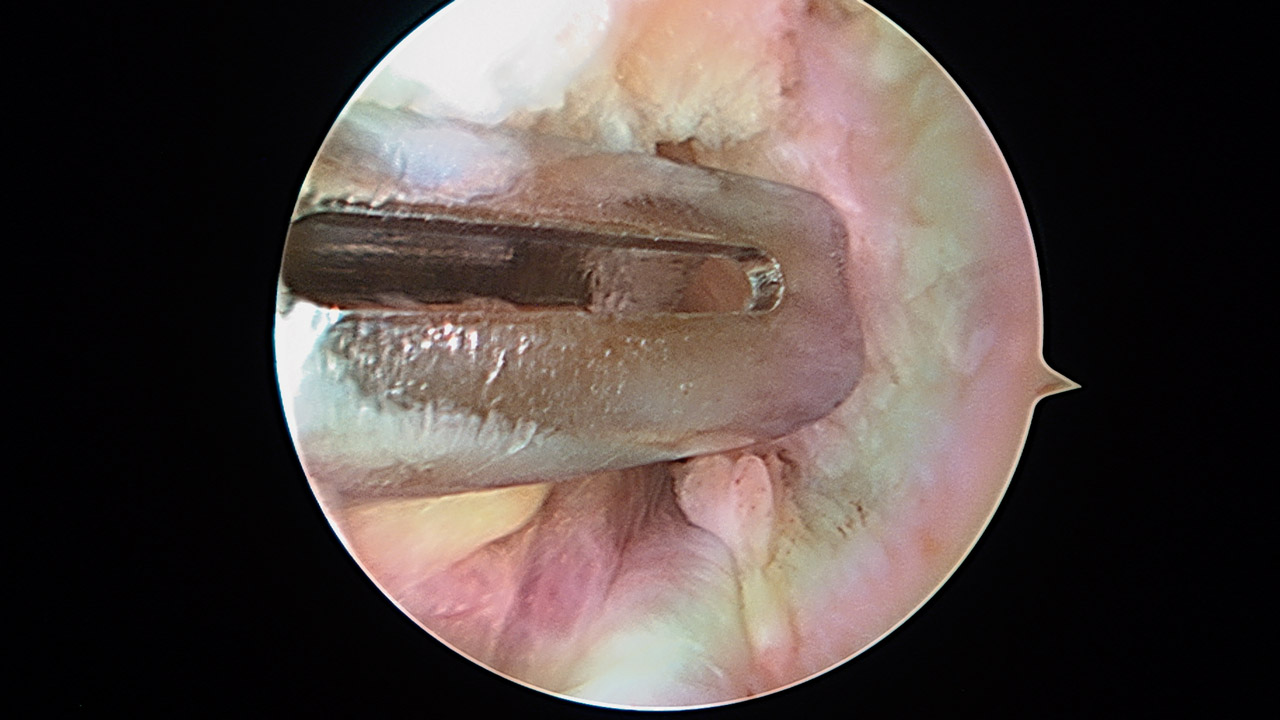

Ligamentoplastia anterior de hombro. Técnica quirúrgica

Anterior shoulder ligamentoplasty. Surgical technique